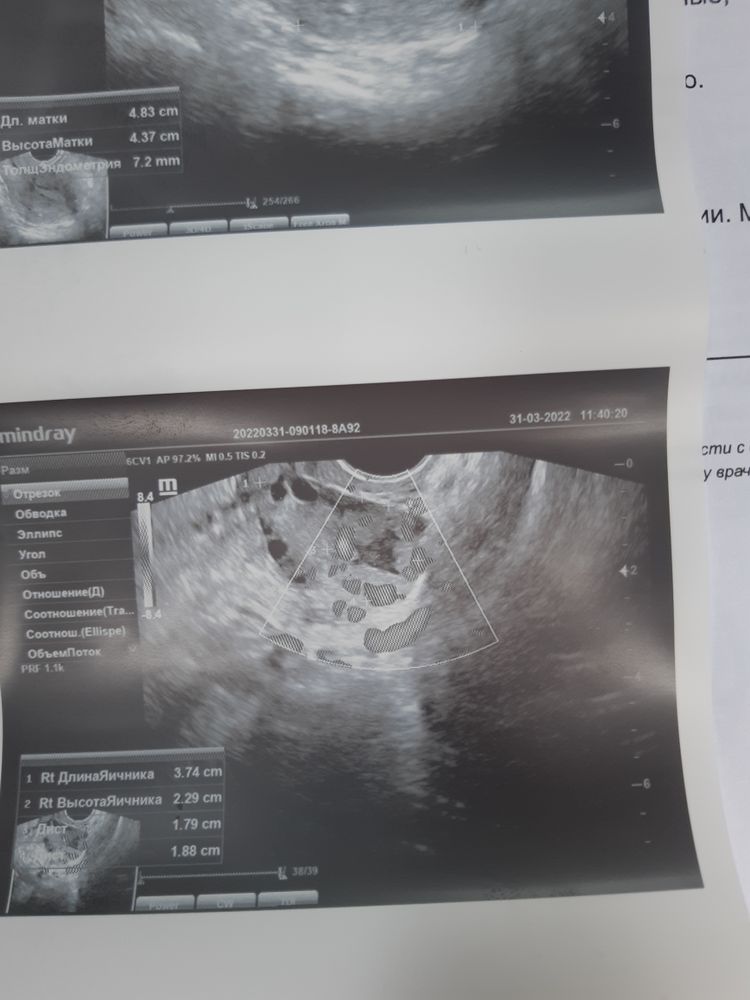

Девочки привет! У меня тут такой вопрос . Нашли в ПЯ жт - 18×18, без жидкости . Г. Предположила, что О была больше 5 дней назад так как нет жидкости в матке. Вопрос : ато по узи следил за жт ? На какой день обычно пропадает эта жидкость ?

Фатима, да это я знаю. Просто была на узи на 27 дц и мне врач сказала что ановуляторный цикл. Я начала дюф. Пропила 10 дней...и 10 дней после последней таблетки ждала м ....они не пришли. А вчера на узи увидели жт 18! Я в шоке .... но по графику выдалась неделя,( 6 дней ) когда па не было. Вот и интересно стало можно как-то по жиой жидкости о определить . Врач говорит примерно неделю или дней 9 назад была о - тогда мы попадаем в эти дни , а если о была 4 дня назад то тогда мы в пролете(